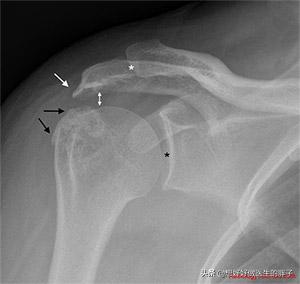

Les douleurs de l'épaule dues au syndrome de l'impaction de la hanche se caractérisent parDouleur associée au mouvement de l'articulation de l'épaule (peut être différenciée de la colonne vertébrale cervicale causant une douleur à l'épaule)Dans certains cas, la douleur peut être provoquée par certains mouvements de soulèvement ou d'abduction des membres supérieurs et, chez certains patients, un cliquetis dans l'épaule est entendu lorsque la douleur est provoquée. Dans ce cas, la présence d'un problème peut souvent être déterminée par une radiographie ou une IRM de l'articulation de l'épaule.Comme vous pouvez le voir ci-dessous, la flèche blanche représente l'ostéophyte de l'acromion dû à l'impaction, et la flèche noire représente l'ostéophyte de la grosse tubérosité de l'humérus, qui impacte l'acromion.(ibid.).